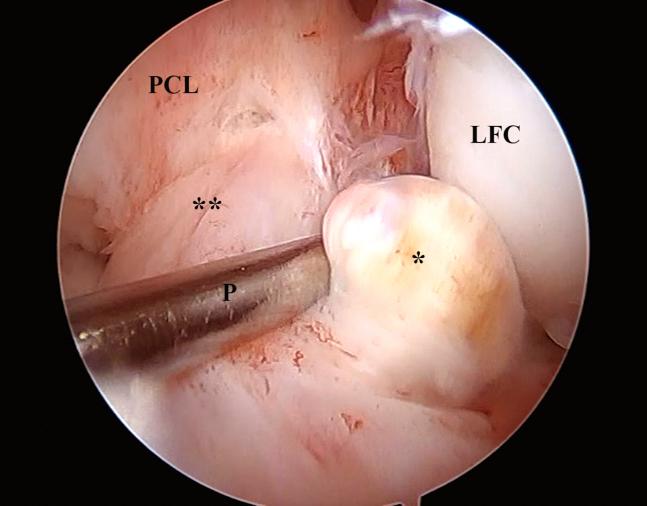

A technique for augmentation of the partial anterior cruciate ligament is presented. The patient is positioned supine with the knee flexed 90°. After addressing intra-articular injuries, the autologous semitendinosus tendon is harvested and measured in a doubled manner; after that, the tibial tunnel is performed in the outside-in direction, of the same diameter of the doubled graft. Both ends of the graft are sutured together, after inserting it through the loop of a suspension device, which is attached in its augmentation piece. A lateral femoral incision is made, to approach the joint through the "over the top" position. A looped thread is introduced inside the joint with the aid of a hook. This thread pulls the graft's sutures through the "over the top" position. A femoral tunnel is then drilled in the lateromedial and caudocranial direction. The suspension device is attached to the anterior tibial cortex and the graft is pulled in the caudocranial direction to the femoral tunnel, where an interference screw is used for fixation.

介绍了一种部分前交叉韧带增强技术。患者仰卧位,膝关节屈曲90°。处理关节内损伤后,取出自体半腱肌腱并对折测量;之后,由外向内方向制作胫骨隧道,其直径与对折后的移植物相同。将移植物两端缝合在一起,通过悬吊装置的环插入,悬吊装置连接在其增强片上。做一个股外侧切口,通过“过顶”位置进入关节。借助钩子将环形线引入关节内。该线将移植物缝线拉过“过顶”位置。然后在股骨外侧向内侧和尾颅方向钻一个股骨隧道。将悬吊装置固定在前胫骨皮质上,将移植物沿尾颅方向拉入股骨隧道,在此处使用挤压螺钉进行固定。